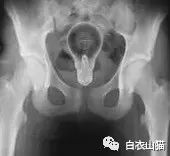

这是做饺子皮用的擀面杖。对,全部塞进去了。你知道怎么看男女吗?看骨盆的角度。